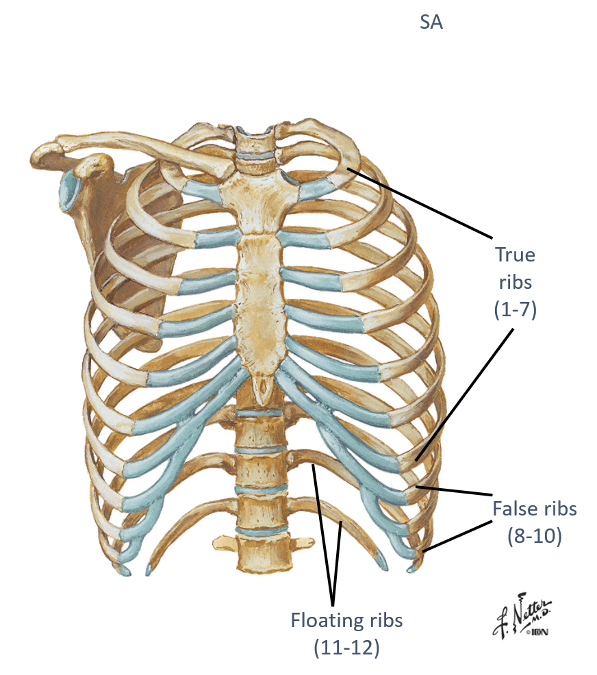

identify the sub-divisions of the ribs (true, false and floating) and describe them?

- True (1-7) – attach “directly” to sternum

- False (8-10) – attach “indirectly” to sternum thru cartilage

- Floating (11-12) – do not attach to the sternum AKA dont even make their way around